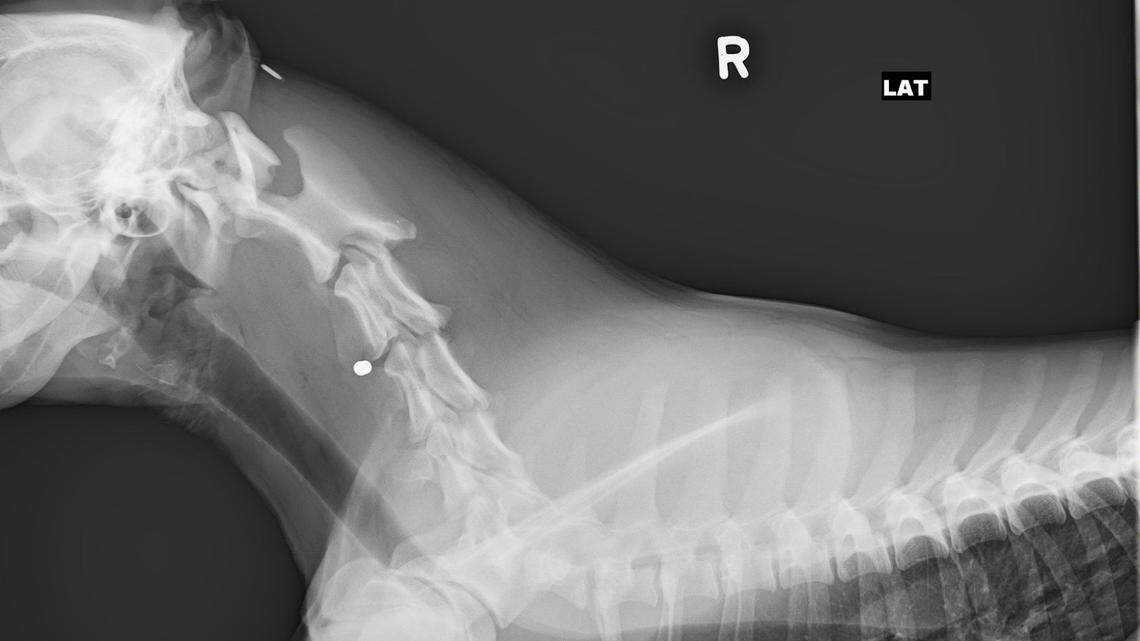

Police said they discovered antifreeze in several dog bowls across an Indiana neighborhood where a dog was shot. Photo by Utica Indiana Police Department

The dog was taken to a nearby hospital on Feb. 18. It is now back home with its owner and “has a long road of recovery ahead,” police said in a Facebook comment.